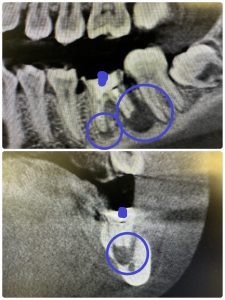

朝から病巣ばっかり

➀

4ヶ月で治る、年齢20代foreigner

右下はインプラントがベスト

私がやれば、悪くなりませんよ!🤪